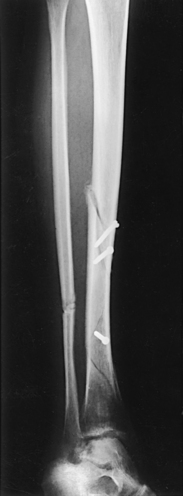

Structures shown: The resulting image shows the tibia, fibula, and adjacent joints (Fig. 6-112).

Fig. 6-112 A, AP tibia and fibula. Long leg length prevented showing entire leg. A separate knee projection had to be performed on this patient. B, Short leg length allowed entire leg to be shown. Spiral fracture of distal tibia with accompanying spiral fracture of proximal fibula (arrows) is seen. This radiograph shows the importance of including the entire length of a long bone in trauma cases. C, AP tibia and fibula on a 4-year-old with neurofibromatosis.